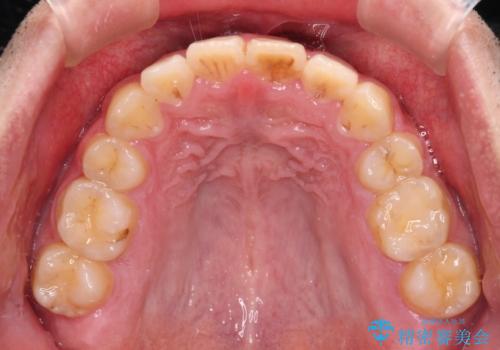

後戻りでデコボコの前歯 インビザライン矯正治療

- 高校時代に行った抜歯矯正が後戻りをしたとのことで来院された患者様です。

再矯正であることから、目立ちにくい装置を希望されたため、インビザラインにて矯正治療を行うこととしました。

下顎骨が左側に変位しているため、正中が合わないことは予想できましたが、歯列が整った後も咬み合わせが安定せず、咬み合わせを落ち着かせるために1年以上の期間を要しました。

噛みにくさの改善に時間がかかってしまうことがインビザラインの欠点の1つといえます。